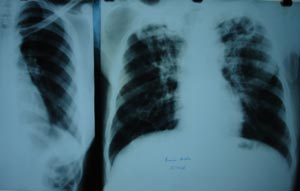

Pulmonary tuberculosis 1

Both upper zones are having extensive fibrosis with Left apex showing a thick walled cavity, suggestive of bilateral koch’s infection.